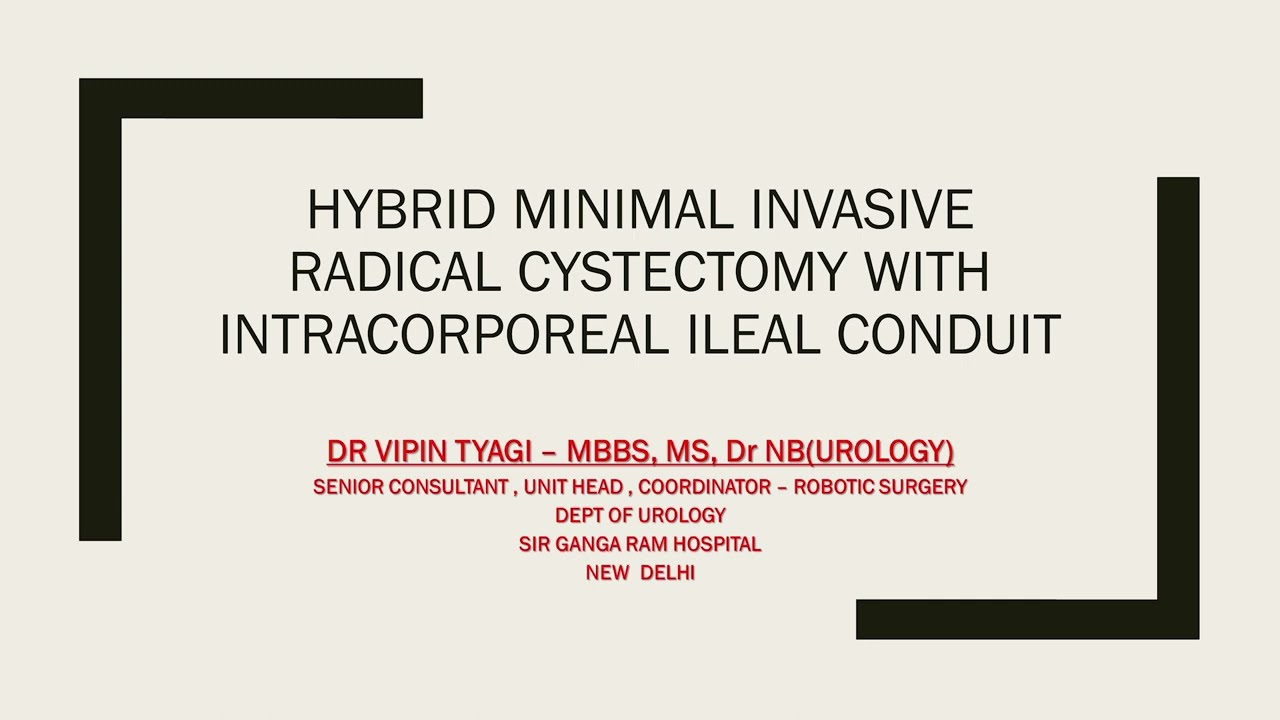

#250 Hybrid robotic radical cystectomy with intracorporeal conduit- Dr. Vipin Tyagi

KS Awards, Robotics, Surgeon ';